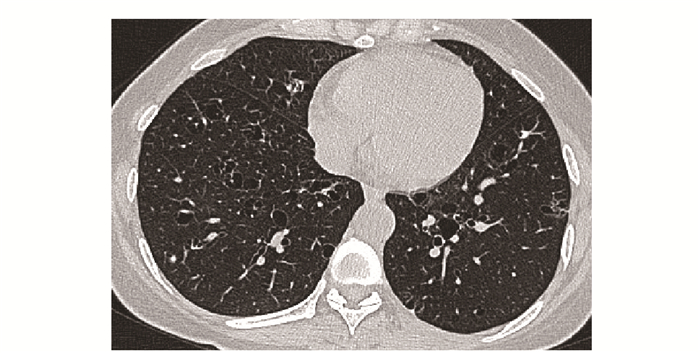

• 摘要: 结缔组织病累及呼吸系统可表现为间质性肺疾病、弥漫性肺泡损伤、肺泡出血、肺血管病变、胸膜病变及气道病变等。其临床表现缺乏特异性, 肺功能和胸部CT是最常用的检查手段。不同结缔组织病累及呼吸系统的影像特征具有相似性, 但又各具特点。本文就结缔组织病呼吸系统受累相关影像表现进行概述, 以提升读者的认知并指导临床实践。

Abstract: Respiratory manifestations of connective tissue diseases include interstitial lung diseases, diffuse alveolar injury, alveolar hemorrhage, pulmonary vascular lesions, pleural lesions and airway disease. Their clinical symptoms were not specific. Pulmonary function test and chest computed tomography come to be the most frequently applied examinations. Different connective tissue diseases involving respiratory system have not only common features but also characteristic imaging patterns. In this paper, imaging manifestations of respiratory diseases associated with connective tissue diseases were reviewed, so as to improve readers' recognition of the diseases and guide clinical practice.